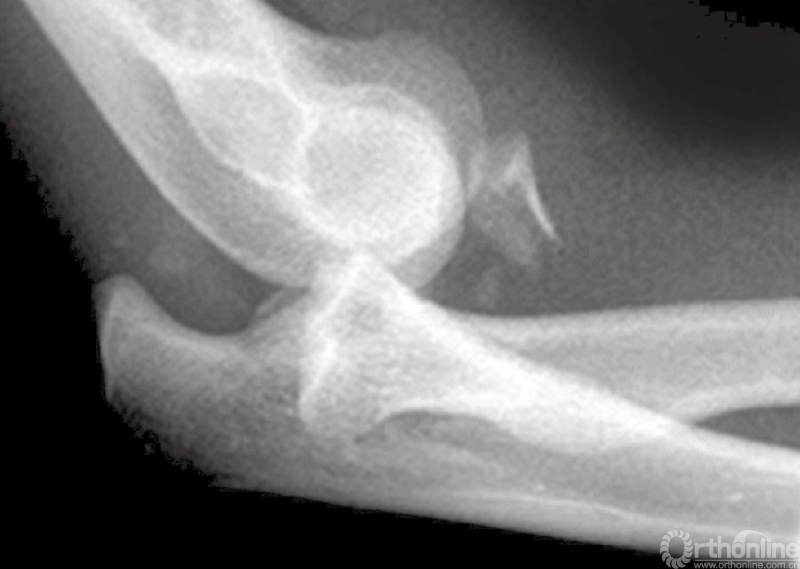

冠状突骨折应拍摄肘关节正位(AP)、侧位片,如果有需要,还应该拍斜位片以明确是否有骨损伤。斜位片对轻微移位的骨折尤为重要,因为肘关节侧位片上桡骨小头和尺骨冠突影重叠,因此冠状突骨折容易和桡骨小头骨折混淆。

为避免这个情况,Greenspan和Norman介绍了肱桡位片(图6和图7)。这个位置可以把桡骨头及冠突区分开,可以提供清晰的冠突、桡骨头、肱桡关节和上尺桡关节。有时普通的X线片难以提供完全确切的诊断依据,这就需要行CT扫描或MRI检查。

图6 肱桡位片拍摄方法

图7 A~C肱桡位片正位片上看似乎是单纯的肱骨小头骨折,事实上在侧位片和肱桡位片上可以看到合并有冠状突骨折